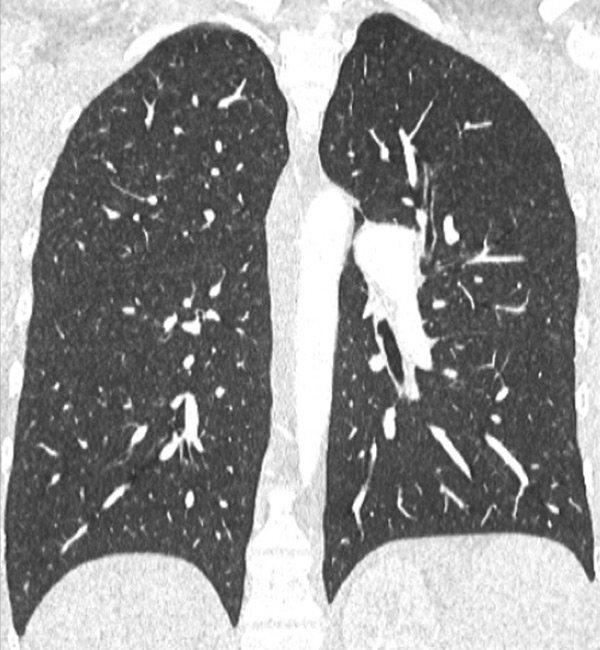

Figure 7

Portopulmonary hypertension in a 16-year-old. No abnormalities were found on morphological computed tomography (A/B), but heterogeneous perfusions were present on the perfusion map (stars, C/D).